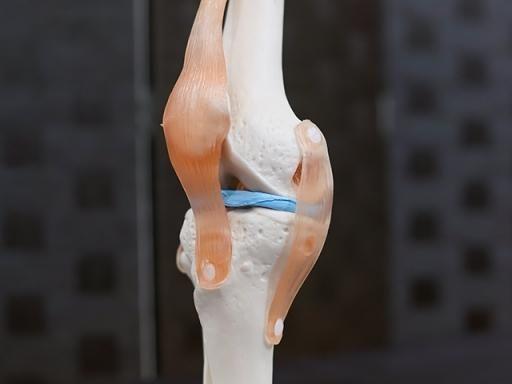

靭帯の損傷

膝の靭帯は、内側、外側、中央の3種の靭帯で膝の安定をさせる重要な部分になります。特に内側の靭帯は伸ばされやすく体を捻った動作の時に痛めれば、内側側副靭帯の損傷が考えられます。また中央の靭帯は十字靭帯といってスポーツで正面からぶつかったり、後ろから乗られたり、自分の体重が膝に乗った際に孫相するのが特徴です。

これらの靭帯を強く伸ばせば、時にギプス固定、断裂に近い損傷を受けている場合は手術の対象になります。

内側半月板

半月板の損傷

特に内側の半月板は非常にケガしやすい構造になっており、スポーツだけでなく老化による半月板の消耗もほとんどが「内側」の半月板になります。半月板は再生能力が低く、重度損傷であればギプス固定、完全損傷であれば手術の対応になる場合もあります。